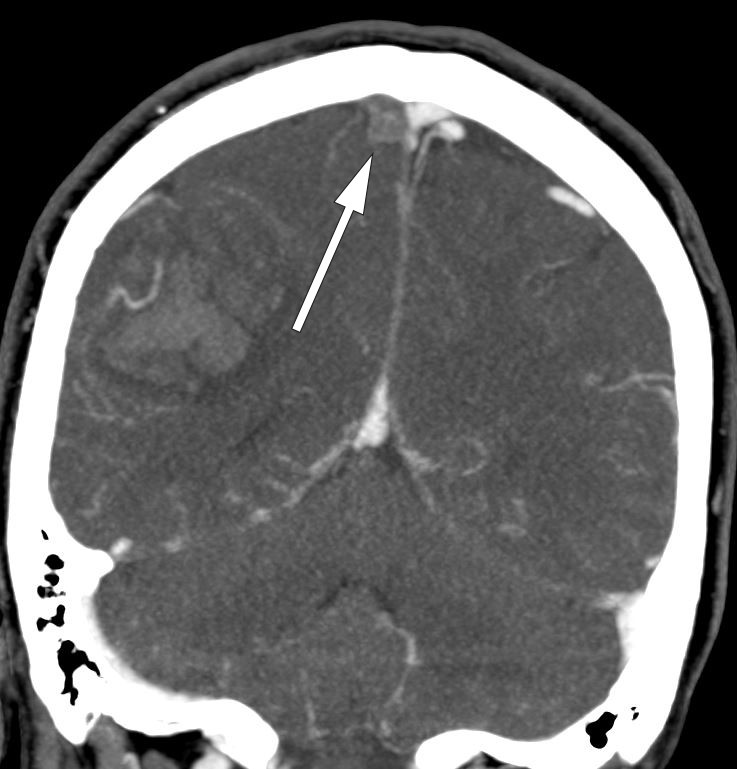

Ved sterk klinisk mistanke om cerebral venetrombose, eller dersom man på CT caput finner lobære parenkymblødninger eller infarktforandringer som ikke følger de vanlige arterielle kargebetene, må cerebral venetrombose mistenkes og ytterligere bildeundersøkelser gjennomføres (1–3). CT caput uten kontrast har dårlig sensitivitet (40–70 %), og tillegg av intravenøs kontrast kan vise en hyperdens fyllingsdefekt i venesinusene (inkludert såkalt tomt deltategn i sinus sagittalis superior), men fortsatt ser man verken direkte eller indirekte tegn på cerebral venetrombose ved CT-undersøkelse hos mer enn 30 % (3, 12).

Både CT- og MR-venografi kan bekrefte diagnosen cerebral venetrombose, men MR-venografi er trolig mer sensitiv i den akutte fasen (3, 13, 14). Hjerneparenkymet, venøse infarkter og blødninger blir bedre fremstilt ved MR-venografi slik at dette er den foretrukne modaliteten (1). Venøse infarkter forekommer hos omtrent 60 % av pasientene og avviker fra de arterielle infarktene ved at deres utstrekning går utover de vanlige kargebetene (3).

Vi takker nevroradiolog Svetozar Zarnovicky ved Radiologisk avdeling, Akershus universitetssykehus for hjelp med bildet som illustrerer denne artikkelen.